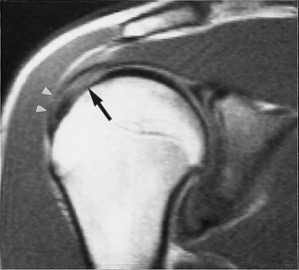

(Слева) Аксиальная Т1FS МР-артрограмма: визуализируется хронический дефект Хилла-Сакса костно-хрящевой импрессионный перелом с выраженным повреждением хряща. Кроме того, пациент перенес разрыв вращательной манжеты, о чем можно судить по наличию жидкости в субакромиально-субдельтовидной сумке.

(Справа) Кососагиттальная FS PDFSE МР-артрограмма: определяется изолированный хрящевой перелом Хилла-Сакса. Несмотря на небольшой размер дефекта, его наличие, тем не менее, свидетельствует о перенесенном переднем вывихе.